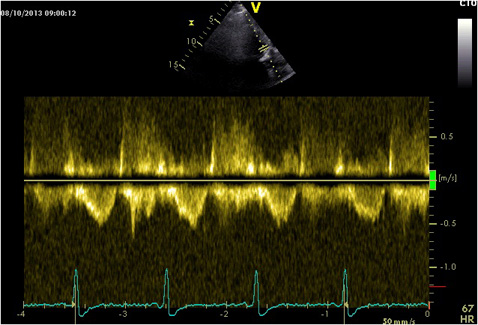

DOPPLER HEMODYNAMICS (1) - CardioEgypt

DOPPLER HEMODYNAMICS (1) QUANTIFICATION OF PRESSURE GRADIENTS and. Vmax. TR gradient. Assessing Hemodynamics RA pressure (using IVC size) Aortic Valve Gradients 1. Peak-to-Peak Gradient (PP) 2. Maximum Instantaneous Gradient (MIG) 3. ... Retrieve Full Source